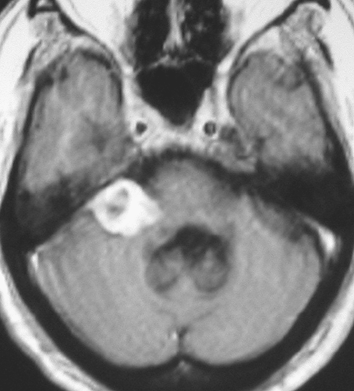

聴神経腫瘍でまず手術が必要なのは巨大なものです。この4枚の写真は私が実際に手術をした患者さんのものです。脳幹部という脳の最も大切なところが腫瘍によって圧迫されて変形しているのが特徴です。右上のものはのう胞性腫瘍なので大きさの割に手術のリスクは高くありませんが,左上のものは実質性で出血性のものですごくリスクが高い手術でした。左下のものは普通のリスク。右下のものは超高難易度のものです。